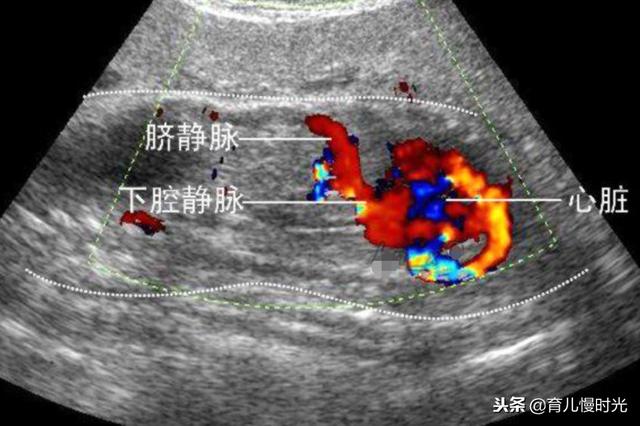

2.彩超检查

在B超的基础上 , 将血流部位变得有颜色 , 可以看出心脏 , 血管和脐带的走向 , 最常见于心脏排畸检查 , 以及孕晚期脐带绕颈的情况观测 。 如果没有彩超 , 普通B超也可以看得清 , 只是需要更多时间和耐心 。